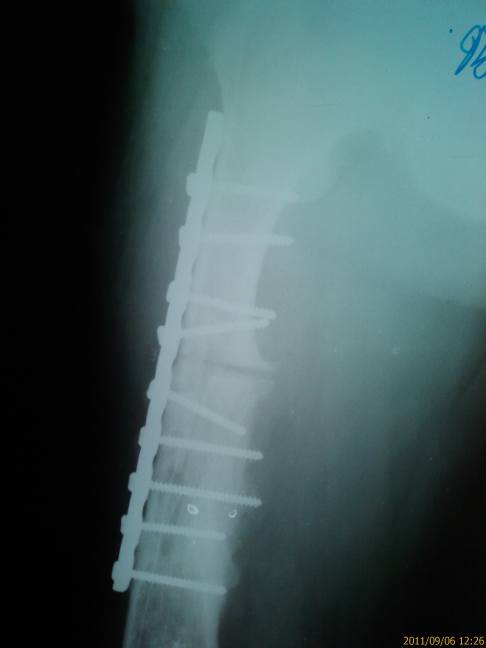

Имя     : Левое бедро.jpg

Тип     : image/jpeg

Размер  : 24090 байтов

Описание: отсутствует

Url     : http://weborto.net:8080/pipermail/ortho/attachments/20110910/89848992/attachment-0003.jpg

16.02.2010г. - Остеотомия бедра в верхней трети и нижней трети. Остеосинтез

аппаратом Илизарова левого бедра. Интрамедуллярный  остеосинтез спицами

левой бедренной кости. 28,042010г. - Проведение дополнитеьных спиц в верхней

трети нижней трети бедра. Перемонтаж аппарата. Кортикотомия бедра в нижней

трети. Аппарат снят:15.06.2010г- дополнительная иммобилизация кокситной